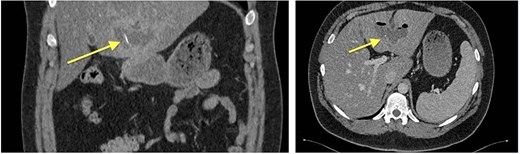

Four months later, a 33-year-old man presented with fever and weakness of unknown origin for 5 days. He was barbecuing a lot in the last weeks, as he was on vacation. Epigastric tenderness was present at admission. Laboratory parameters showed elevated inflammatory markers. CT scan (Fig. 3) showed a liver abscess with a metal foreign body.